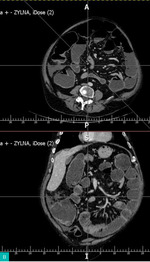

Diagnostyka: Wykonuje się przeglądowe zdjęcie RTG jamy brzusznej w celu potwierdzenia niedrożności (ryc. 1 i 2) i/lub tomografię komputerową (TK) ujawniającą rozdęte pętle jelit powyżej guza (ryc. 3).